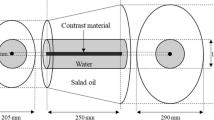

Quantitative measurements of the CT images were performed with the use of profile curves with image J software using the conventional angiography as a Ref. [16].

The actual measured profile curves were obtained by setting the square region of interest (ROI) across the CT images at the same position in all three image data sets, reconstructed with FBP, AIDR3D, and FIRST from the 30 patients (Fig. 1a). We placed the square ROI on the main trunk, superficial branch, and deep branch of the cystic artery. The X-axis of the square ROI represents distance along the line and the Y-axis that is normally wider than one pixel represents the averaged pixel intensity. On the actual measured profile curve, the ΔCT number in three reconstructions was calculated using the formula as below:

where HU peak is the maximum CT number of the profile curve. In addition, we selected the higher CT number of the two curve bases as an HU background to minimalize the influence of the fat density (Fig. 1b).

a Square region of interest (ROI) was placed across CT angiograms (the main trunk, superficial branch, and deep branch of the cystic artery) at the same position in the three image data sets, reconstructed with FBP, AIDR3D, and FIRST. b On the actual measured profile curve, the ΔCT numbers in three reconstructions were calculated from the HU peak and HU background (higher curve base). c On the normalized profile curve, we measured the width of the curve one-tenth above the higher base as the full-width at tenth-maximum (FWTM) in the three reconstructions

The CT number of the peak and background of the actual measured profile curve was then taken to calculate the normalized profile curve. On the normalized profile curve, we measured the width of the curve one-tenth above the higher base as the full-width at tenth-maximum (FWTM) (Fig. 1c).